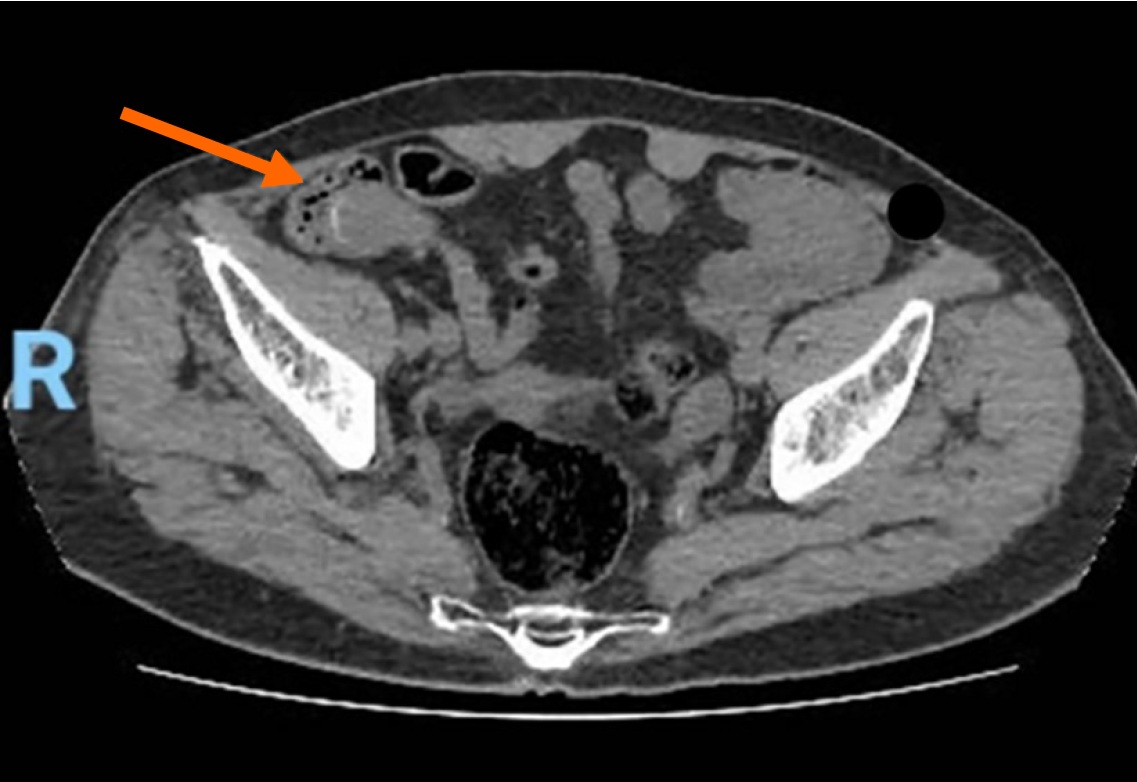

Figure 3 Computed tomography scan with intravenous contrast showing a well-circumscribed, low fluid attenuation tubular-shaped structure, seen in continuation with the base of the cecum, grossly measuring 64 mm × 29 mm × 28 mm, corresponding to the appendix (orange arrow).